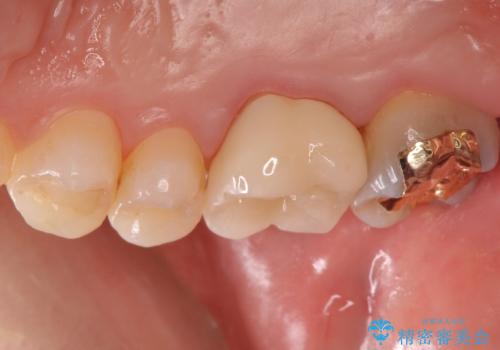

セラミックは劣化で変色することがありません。

表面も滑沢で汚れが付着しにくく、適合の良いセラミッククラウンは治療後の虫歯リスクを抑えてくれます。